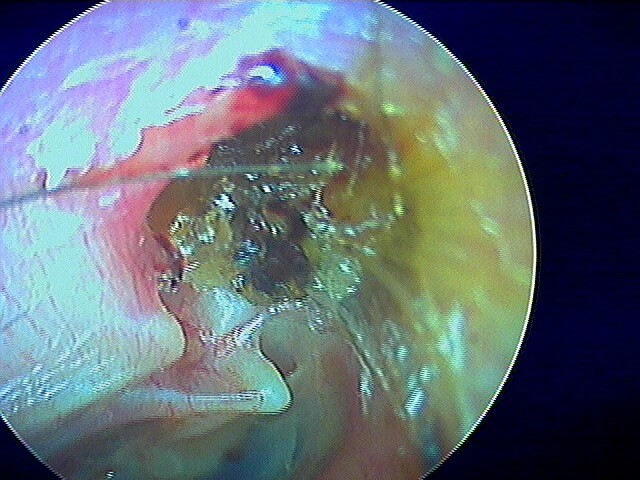

Dans ma pratique, je vois plus d'otomycose à Aspergillus niger, très caractéristique avec ces points noirs.

La même oreille après aspiration: